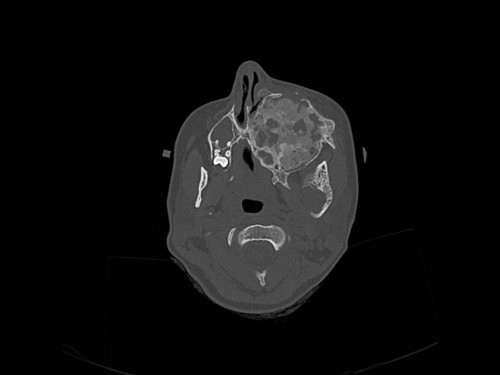

Knochendeformitäten seit der Geburt

Fall-ID: 712

ICD: M85.09

Autor*in: Sandra Klipp

Eine 16-jährige Patientin kommt in eine MKG-chirurgische Praxis zur Abklärung der weiteren Vorgehensweise bzgl. ihrer Erkrankung.

Sie betrachten die angefertigten Röntgenbilder. Welche der folgenden Röntgenbefunde ist korrekt? Ossäre Auftreibungen im Bereich …

- A… der Mandibula links.

- B… des Os frontale links.

- C… des Os zygomaticum links.

- D… des Os temporale links.

- EAlle genannten Aussagen sind korrekt.

Bildgebung - OPAN 2004